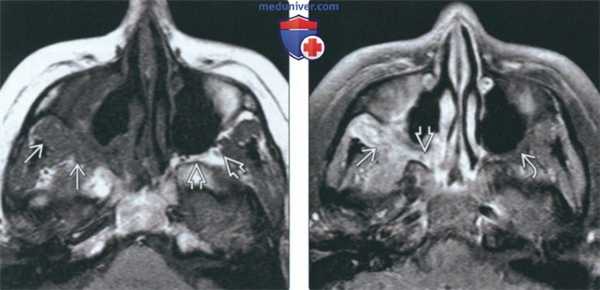

(Слева) При корональной КТ у пациента с ГПА, хроническим риносинуситом и жалобами на головную боль определяется перфорация носовой перегородки, а также сливное снижение пневматизации решетчатых пазух с обеих сторон в сочетании с деструкцией решетчатой пластинки.

(Справа) При корональной МРТ у этого же пациента определяется диффузное утолщение слизистой оболочки верхнечелюстных и решетчатых пазух, перфорация носовой перегородки, двухсторонняя деструкция носовых раковин и наружных стенок носовой полости. Обратите внимание на контактный лахименингит передней черепной ямки.

(Слева) На аксиальной КТ без КУ определяется деструкция верхних отделов носовой перегородки, перегородок между ячейками решетчатой кости, обеих глазничных пластинок (двухстстроннее поражение глазницы при гранулематозе).

(Справа) На корональной МРТ (Т1 ВИ) у этого же пациента определяется нарушение анатомии структур полости носа и утолщение стенок верхнечелюстных пазух. Жировые пластинки между патологически измененными мягкими тканями и медиальной прямой и верхней косой мышцами плохо различимы.

(Слева) На корональной МРТ (Т1 ВИ) у пациента с ГПА определяется одноаороннее поражение правой верхнечелюстной пазухи. Патологическое содержимое распространяется из просвета пазухи в жевательное пространаво. Обратите внимание на замещение нормального «жирового» сигнала за пазухой справа и сравните с неизмененной левой стороной.

(Справа) На аксиальной МРТ (Т1ВИ FS) у этого же пациента определяется контрастирование патологических мягких тканей позади пазухи и в крылонебной ямке. Обратите внимание на подавление сигнала в жировой клетчатке слева (норма).